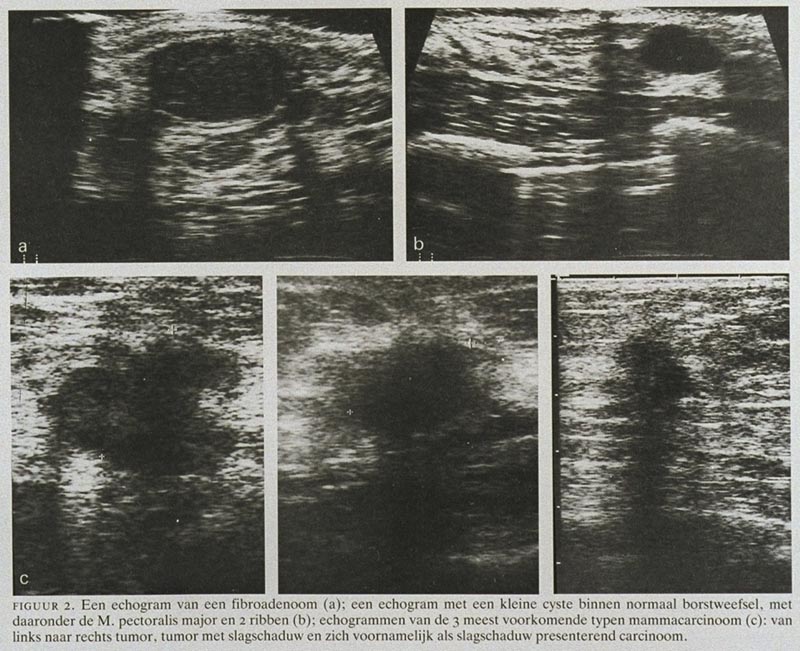

Het goede nieuws is dat de meeste cystes goedaardig zijn. Ze zijn dus niet kwaadaardig, oftewel, ze zijn geen kanker. "Maar hoe weet ik dat dan zeker?" hoor ik je denken. Nou, dat is waar de artsen en de echo om de hoek komen kijken. Ze kijken naar de vorm, de grootte, de inhoud en de randen van de 'waterballon'. Een gladde, ronde ballon is vaak geruststellend. Alsof-ie net vers van de kermis komt!

Op een echo kan een tumor er anders uitzien dan een cyste. Vaak heeft hij een onregelmatige vorm, vastere structuur en soms ook bloedvaten eromheen. Maar eerlijk is eerlijk, op een echo is het niet altijd 100% zeker te zeggen of iets goedaardig of kwaadaardig is.

De Echo: Een eerste indruk

De echo is dus een belangrijk hulpmiddel om een eerste indruk te krijgen van wat er zich in je lichaam afspeelt. Het kan een cyste of een tumor opsporen, maar het kan niet altijd met zekerheid zeggen wat het precies is. Zie het als een selfie die je maakt: je ziet jezelf, maar je innerlijk kun je er niet mee vangen.

Dus, wat is het verschil tussen een cyste en een tumor op een echo? Een cyste is meestal een onschuldig waterballonnetje, terwijl een tumor een abnormale groei van cellen is die goedaardig of kwaadaardig kan zijn. Een echo kan een indicatie geven, maar verder onderzoek is vaak nodig om zekerheid te krijgen.